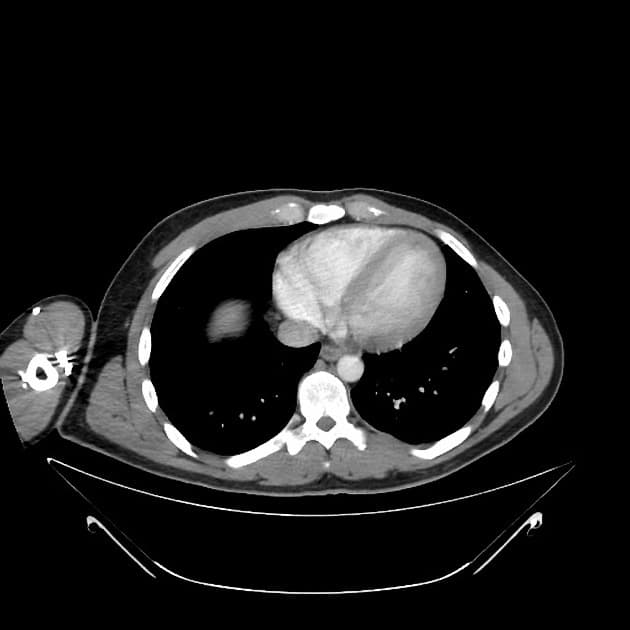

- 1.Vết rách gan kèm máu tụ dưới vỏ

- 2.Tổn thương nhu mô gan với thoát thuốc cản quang hoạt động

- 3.Tổn thương mạch trung tâm liên quan tĩnh mạch gan hoặc nhánh cửa

- "Độ I–III biểu hiện các vết rách hoặc máu tụ ngoại biên, trong khi độ IV–V liên quan tổn thương nhu mô trung tâm hoặc chấn thương mạch máu lớn."

- "Thoát thuốc cản quang hoạt động trên CT là dấu hiệu hình ảnh quan trọng cho thấy chảy máu đang diễn ra và có thể ảnh hưởng đến quyết định điều trị."